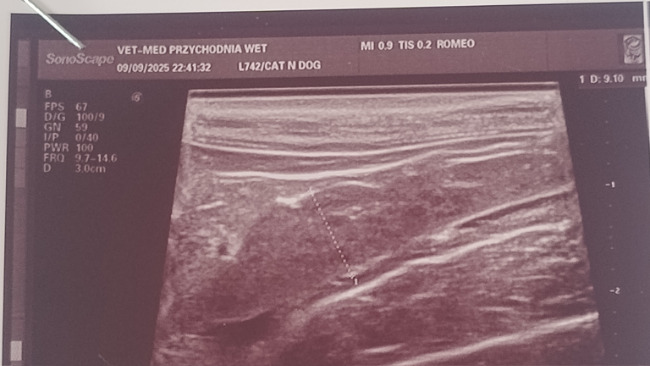

Romeo to nasz 11-miesięczny kotek, który walczy o życie. Jego historia jest pełna bólu, ale również ogromnej nadziei. Romeo zmaga się z ciężką chorobą – FIP (zakaźną chorobą otrzewnej kotów), ma dodatkowo stwierdzoną białaczkę, a co za tym idzie bardzo głęboką anemie. Jest już po dwóch transfuzjach krwi, które pomogły mu przetrwać najtrudniejsze chwile. Kot był hospitalizowany przez 3 dni, a koszty leczenia przekroczyły już 8 tysięcy złotych.